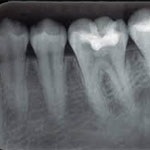

ضمنا تالیف کتاب رادیوگرافی پانورامیک دندان نیز جزو فعالیتهای علمی ایشان می باشد . علاوه بر این دکتر نازنین بصیری بعنوان سخنران در دوره های مختلف بازآموزی و کنگره های بین المللی شرکت نموده است . ایشان از سال 1388 تاکنون در مرکز تخصصی رادیولوژی دهان ، فک و صورت خود واقع در شهر تهران ، خیابان ستارخان مشغول فعالیت بوده و سعی بر این داشته که با تکیه بر دانسته ها و تجارب علمی خود ، رادیوگرافی های دندان و فک وصورت را با بالاترین کیفیت و ارزش تشخیصی به مراجعه کنندگان محترم ارائه نماید .